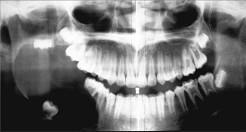

问题 男,18岁,右颌下区反复肿胀半年,2天前再次发作,病程进展快,出现张口受限。X线片示右下颌角区沿颌骨长轴有单囊阴影,包绕右下颌第三磨牙牙冠。该病人最可能的诊断是 ( )

选项 A.右下颌骨中央性癌 B.右下颌骨骨髓炎 C.右下颌造釉细胞瘤 D.右下颌角化囊肿继发感染 E.右下颌骨含牙囊肿

答案 E